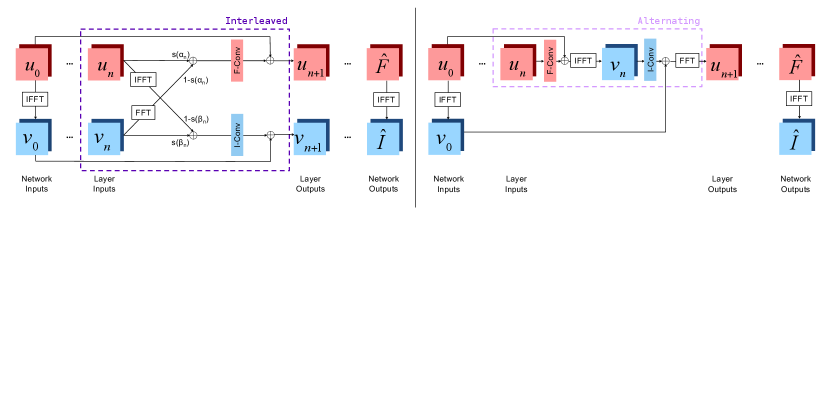

Fig. 2 illustrates the layer structures of the two joint networks. We use to denote the frequency space input and to denote the image space input of layer . Thus, and represent the frequency space and image space inputs to the network.

In the Interleaved setup, layer inputs are combined via learned, layer-specific mixing parameters and that parameterize the sigmoid function to constrain the mixing coefficients to (0,1):

| (1) | ||||

Real and imaginary parts of inputs are represented as separate channels at each layer and are joined appropriately to form complex numbers when computing the Fourier transform or its inverse. Next, the layer applies batch normalization (BN), a convolution, and an activation function with a skip connection to produce the outputs:

| (2) | ||||

where are learned frequency space convolution weights and biases, are learned image space convolution weights and biases, and and are activation functions specific to the frequency space and image space network components, described later in this section.

This layer architecture is a generalization of networks that operate purely in frequency space, obtained by choosing and , and of networks that operate purely in image space, that arise when and . When and , this layer represents a function that cannot be expressed solely via pure image or frequency space convolutional layers that do not invoke the Fourier transform or its inverse. Note that the frequency output of layer is not required to be the Fourier transform of the layer’s image output , only that the mixing is applied to either two frequency space outputs or two image space outputs. This additional flexibility ensures that and are not entirely redundant and the network learns the right features to capture MRI structure based on the input data and the task at hand.

In the Alternating setup, each layer sequentially incorporates frequency and image space convolutions with the appropriate batch normalization and activation function:

| (3) | ||||

i.e., the reconstruction alternates between convolutions in the frequency and image space. A version of this architecture was previously introduced as part of a task-specific network for undersampled reconstruction (Zhou and Zhou, 2020).